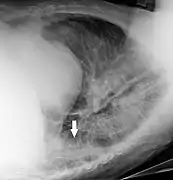

A hip fracture (black arrow) next to a skin fold (white arrow).

Bed sheets looking like lung opacities on a chest radiograph